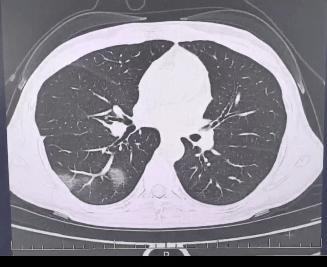

检查结果显示虚拟币,

程女士的好几叶肺

都出现了“白肺”现象虚拟币,

指间血氧饱和度只有 88%虚拟币,

血心肌酶谱、肌钙蛋白的指标、肝功能的指标

也出现了明显的异常虚拟币。

确诊流感(重型)虚拟币!

图源:杭州市第三人民医院微信公众号